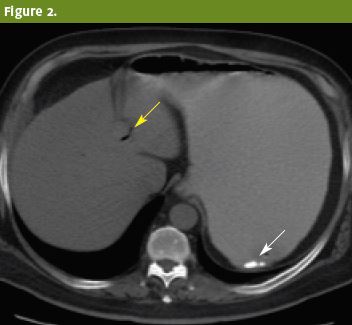

Surgery was consulted for gallstone ileus with distal jejunal obstruction (Figure 2, Figure 3). Patient was reexamined by the surgery team, who noted abdominal distension and guarding. A nasogastric tube was placed, and patient was taken to the operating room with a preoperative diagnosis of gallstone ileus, gastric outlet obstruction, jejunal partial obstruction, and cholecystoduodenal fistula.

Figure 2. Upright view and computed tomography of the abdomen after administration of positive oral contrast show a dilated gastric lumen and retention of contents secondary to gastric outlet obstruction (solid arrow). Paucity of gas in the small bowel and pneumobilia (hollow arrows) are common findings in Bouveret syndrome.